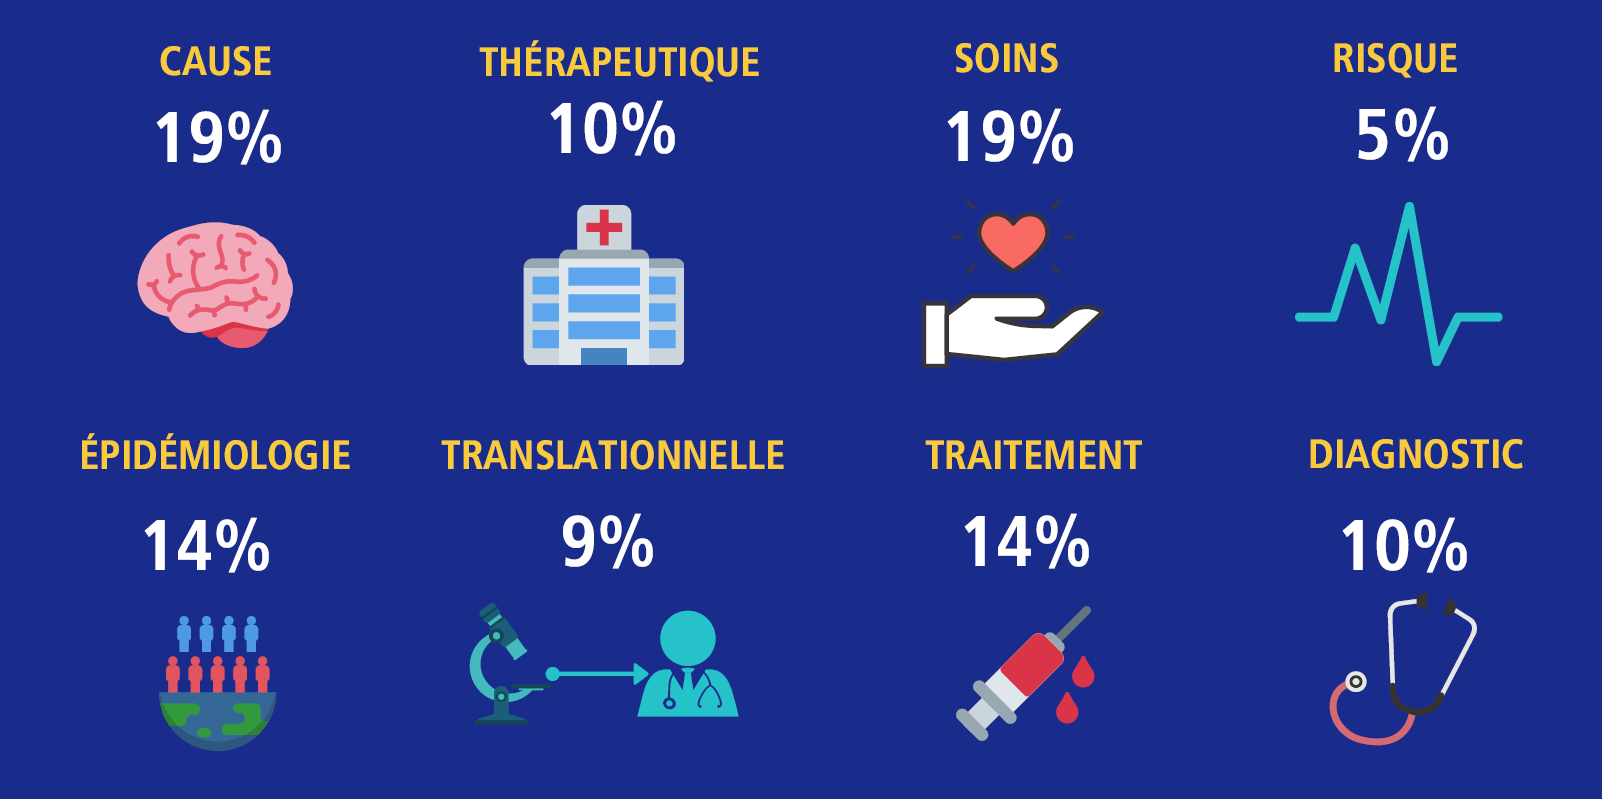

En 2019, le PRSA est passé à un système de concours ouvert qui se concentre sur diverses priorités : science fondamentale, clinique, services de santé et santé de la population. Les demandes portant sur d’autres aspects de la recherche sur les troubles neurocognitifs, comme les causes, la prévention, le risque, la technologie, les sciences sociales et les interventions psychosociales sont également prises en compte.

Découvrez les huit priorités de financement du PRSA et la manière dont elles sont pondérées lors de l’attribution des fonds grâce à l’infographie ci-dessous.